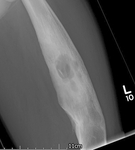

Osteomyelitis

A 62-year-old man suffered an open tibial fracture, which became infected after internal fixation. He continued with intermittent discharge of pus from the front of his tibia for 21 years. Imaging confirmed the presence of chronic osteomyelitis with a central area of dead bone (sequestrum)

Courtesy of the Oxford Bone Infection Unit; used with permission